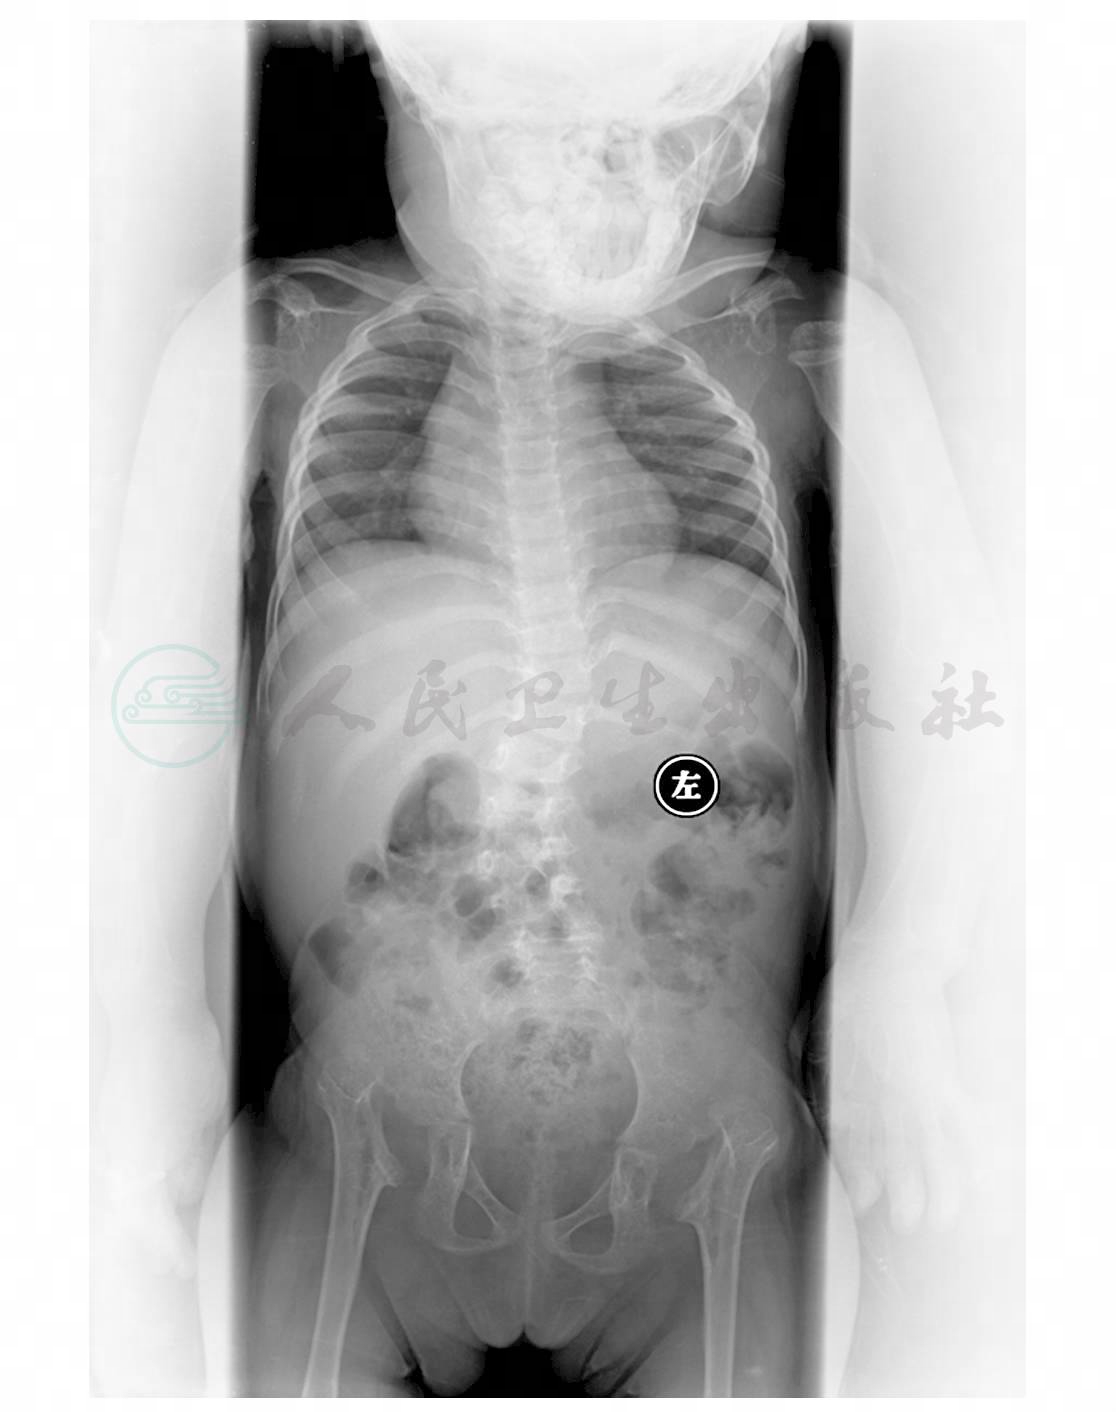

图2 双髋关节、双膝关节及双肩关节脱位,双髋臼发育差

女,3岁,因运动发育异常近3年就诊。体格检查:身材矮小,不能站立,发育落后,营养中等,智力一般,全身皮肤弹性明显差,面容特殊,双眼距增宽,双巩膜蓝染,鼻梁塌陷,鼻孔大略外翻,头围46cm,囟门已闭;听力正常,甲状腺无肿大。胸廓对称,胸围45cm,肋缘外翻,双肺呼吸音清,心音有力律齐,未闻及病理性杂音。全腹平软,肝肋下2cm。胸腰段脊柱以第2腰椎为中心向右侧弯曲,四肢关节松弛,肌张力弱,肌力2~3级,双髋关节外展(+),双髌骨外移,双膝不稳定,双足扁平(图1~图5)。